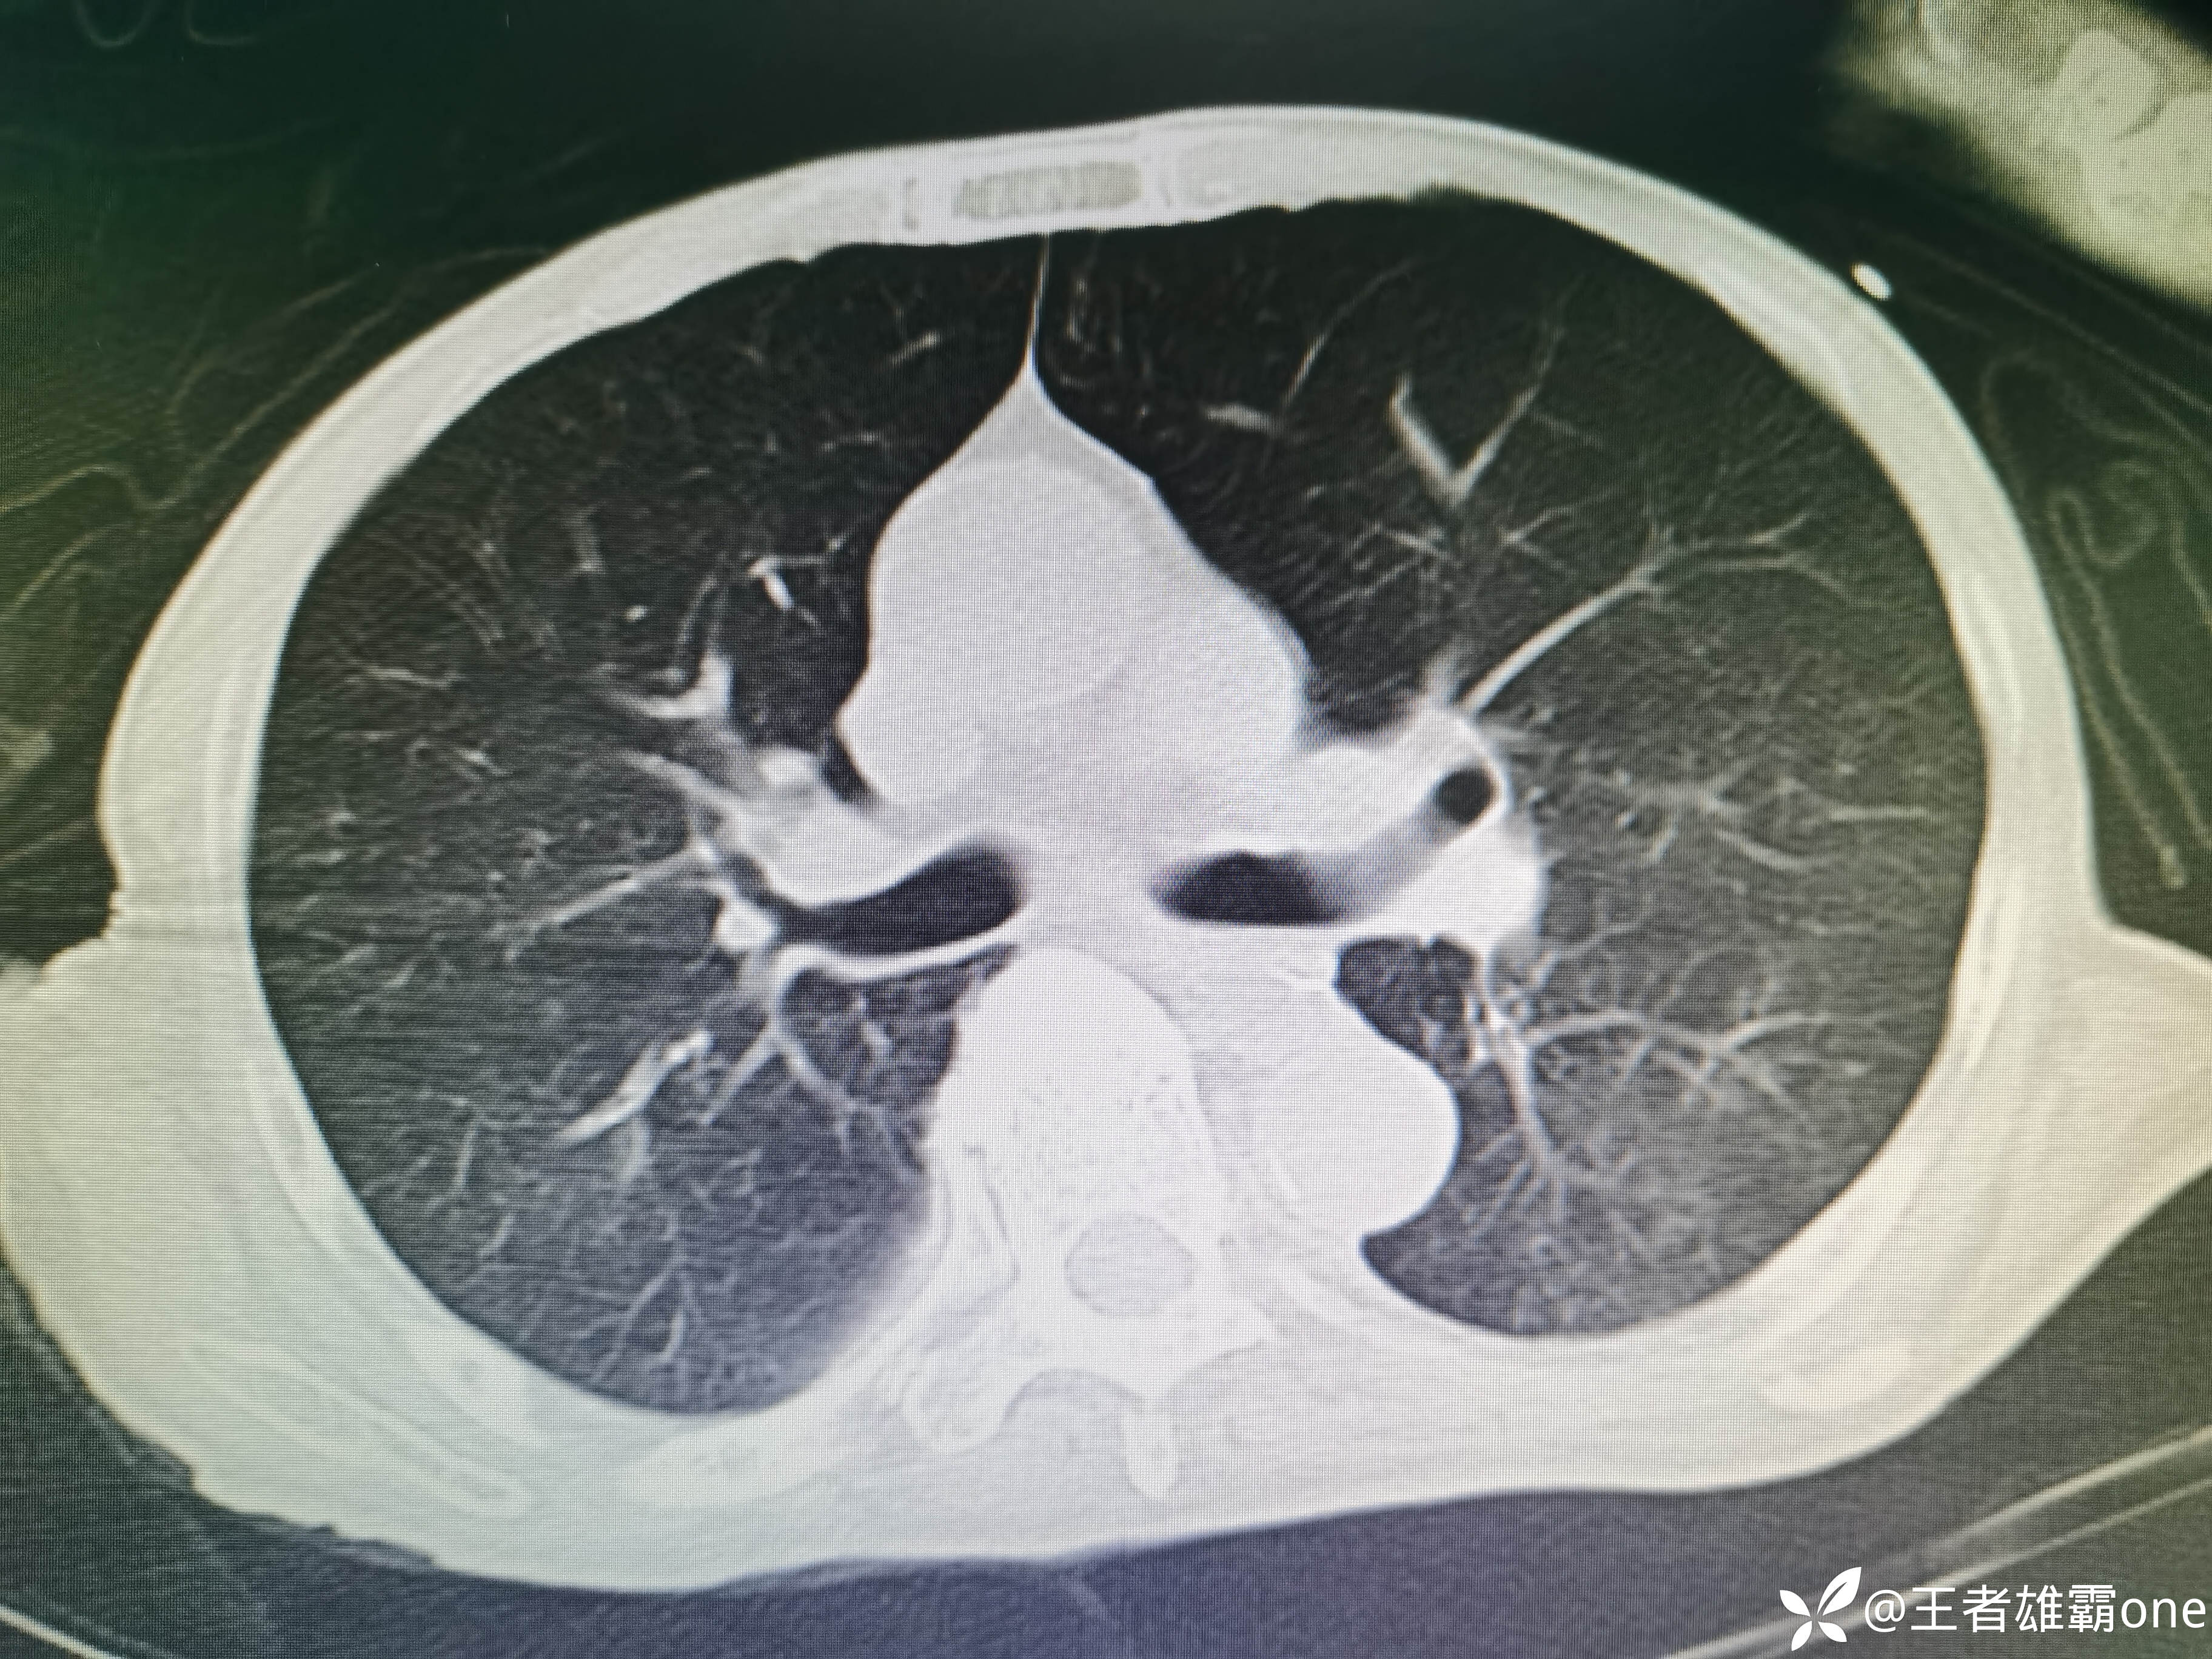

入院时胸部CT:

具体图片: